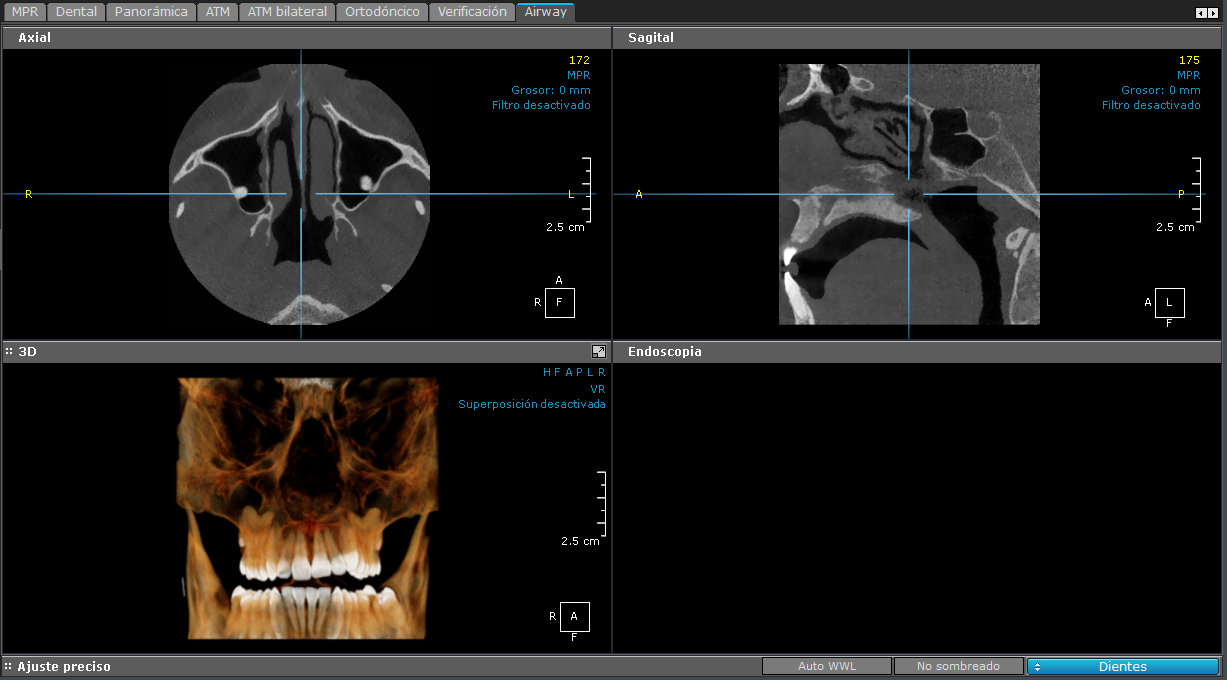

vías Aéreas

Se lleva a cabo para evaluar enfermedades de la cavidad nasal y los senos paranasales.

Disponible en 2D y 3D.